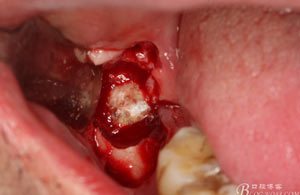

圖8.刮除牙冠表面的肉芽組織后,可見(jiàn)48 的牙冠

圖9.高速牙鉆分牙:

圖10.先頰舌向橫斷、然后再把牙冠近遠(yuǎn)中向縱分

圖11. “T”型的分牙。